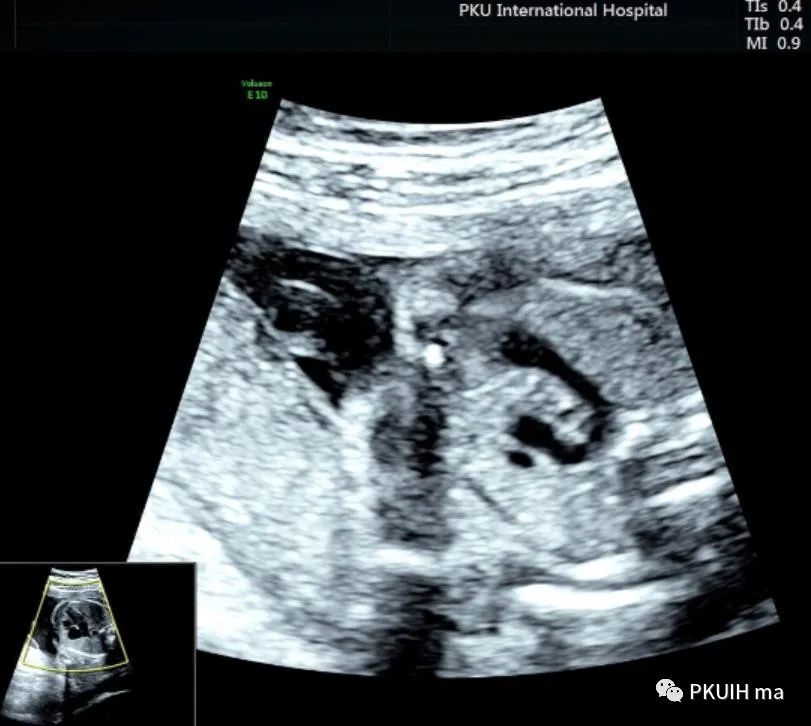

下面几张图都是右位主动脉弓、左动脉导管合并左锁骨下动脉迷走的病例,患儿出生后随访均无明显临床症状

主动脉弓走行于气管的右侧,与左位的动脉导管形成“U”型环(不完全血管环),包绕气管和食管。主动脉冠状切面可见左锁骨下动脉起自于主动脉弓降部,向左肩部走行。

右弓左导管是左位主动脉弓在左锁骨下动脉与左颈总动脉起始处之间退化,形成右弓,左位动脉导管存在于左锁骨下起源区域,右位动脉导管退化,从而形成左向右环绕气管的血管环。右位主动脉弓依次发出左颈总动脉、右颈总动脉、右锁骨下动脉及迷走的左锁骨下动脉。在个别情况下,左锁骨下动脉也可以通过Kommerell憩室的动脉管道直接起源于降主动脉。右位主动脉弓可以是复杂先心的一部分,也可以孤立存在。三血管气管切面是诊断右位主动脉弓的重要切面,结合血流显像可以鉴别右弓的三种类型。